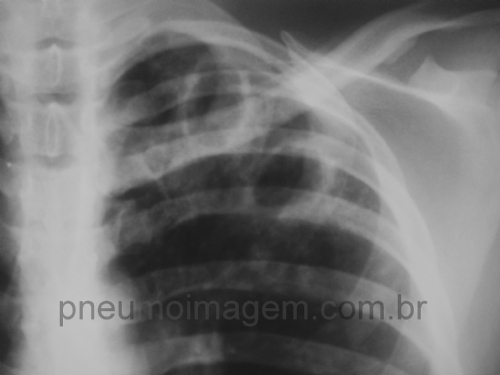

DIAGNÓSTICO E TRATAMENTO DA TUBERCULOSE RESISTENTE A FÁRMACOS: FAÇA O DOWNLOADSão apresentadas as Diretrizes elaboradas pela Sociedade Espanhola de Pneumologia e Cirurgia Torácica (SEPAR), para o diagnóstico e tratamento da tuberculose com resistência a fármacos. O documento inclui recomendações para: 1. Diagnóstico da tuberculose com resistência a fármacos; 2. Bases do tratamento de todas as formas de tuberculose, tanto sensíveis quanto resistentes aos fármacos; 3. Classificação racional dos fármacos com atividade frente ao M. tuberculosis; 4. Tratamento da tuberculose segundo o padrão de resistências; 5. Papel da cirurgia; 6. Controle ao longo do tratamento e avaliação de resultados.